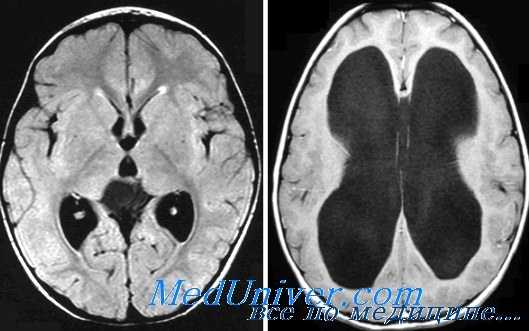

Дополнительными методами диагностики хронической дизрезорбтивной гидроцефалии являются:

1. МРТ головного мозга. Помимо расширенных желудочков с пери-вентрикулярным лейкоареозом, при МРТ определяются еще два признака, патогномоничных для хронической ГЦФ: сужение парагиппокампальных щелей без признаков атрофии гиппокампа и истончение валика мозолистого тела.

2. Фазоконтрастная МРТ головного мозга. Проведение фазоконтрастной МРТ позволяет выявить так называемый неэффективный ток ЦСЖ по водопроводу мозга, состоящий в снижении MP-сигнала в области сильвиева водопровода, который коррелирует с пульсацией волн ЦСЖ. Доказана корреляция между снижением «знака неэффективного тока ЦСЖ по водопроводу мозга» и послеоперационным исходом. Улучшения после имплантации шунта у таких больных достигают в 88% случаев.